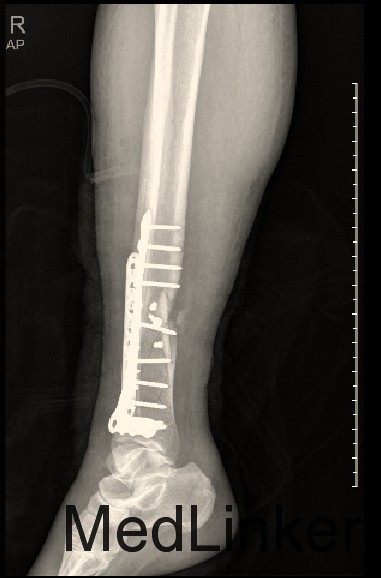

#骨科科室play# 同一平面的胫腓骨骨折

车祸伤至小腿肿胀伴活动受限半天

右小腿肿胀,皮下淤血,骨折断端异常活动,踝关节活动受限,骨檫音(+),足背动脉可及,末端皮肤感觉可

胫腓骨骨折(同一平面) 切开复位内固定术

1.同一平面与不同平面的胫腓骨骨折治疗策略有何不同 2.该例患者胫骨是否可以运用髓内钉?如果使用钢板,内侧或外侧? 3.腓骨骨折的手术指征?